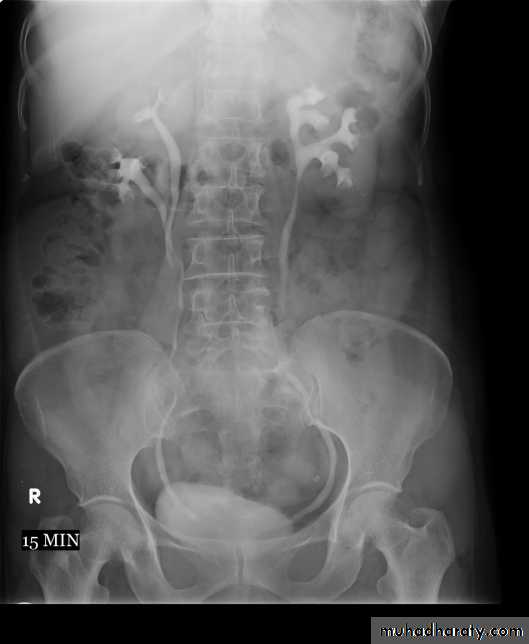

B. Films taken after injection of contrast’ medium:

A series of x-ray films are taken after injection of the contrast.

Each film is taken at a time interval determined by the radiologist who is supervising the procedure.

3. After 10 minutes with compression, to get better distention of the pelvis and calyces.

4. Full length film after release of compression .